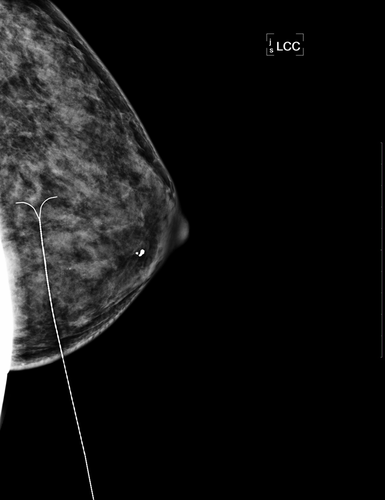

乳腺脓肿穿刺,可以用来诊断是否患上乳腺脓肿,同时,这也是用来治疗乳腺脓肿的方式。乳腺脓肿穿刺的适用范围是比较小的乳腺脓肿,对于比较大的乳腺脓肿,是需要进行手术的。那么,乳腺脓肿穿刺多久能好?

乳腺脓肿穿刺,一般来说,如果恢复的比较好的话,需要两周左右的时间就能好。刚开始乳腺脓肿的脓液比较多的时候,需要每天都抽吸一遍,等到脓液慢慢减少的时候,可以隔天抽吸一遍,或者间隔三天再抽吸一遍。如果不容易抽吸的话,可以在脓腔内注射生理盐水,将脓液稀释后就有利于抽吸。